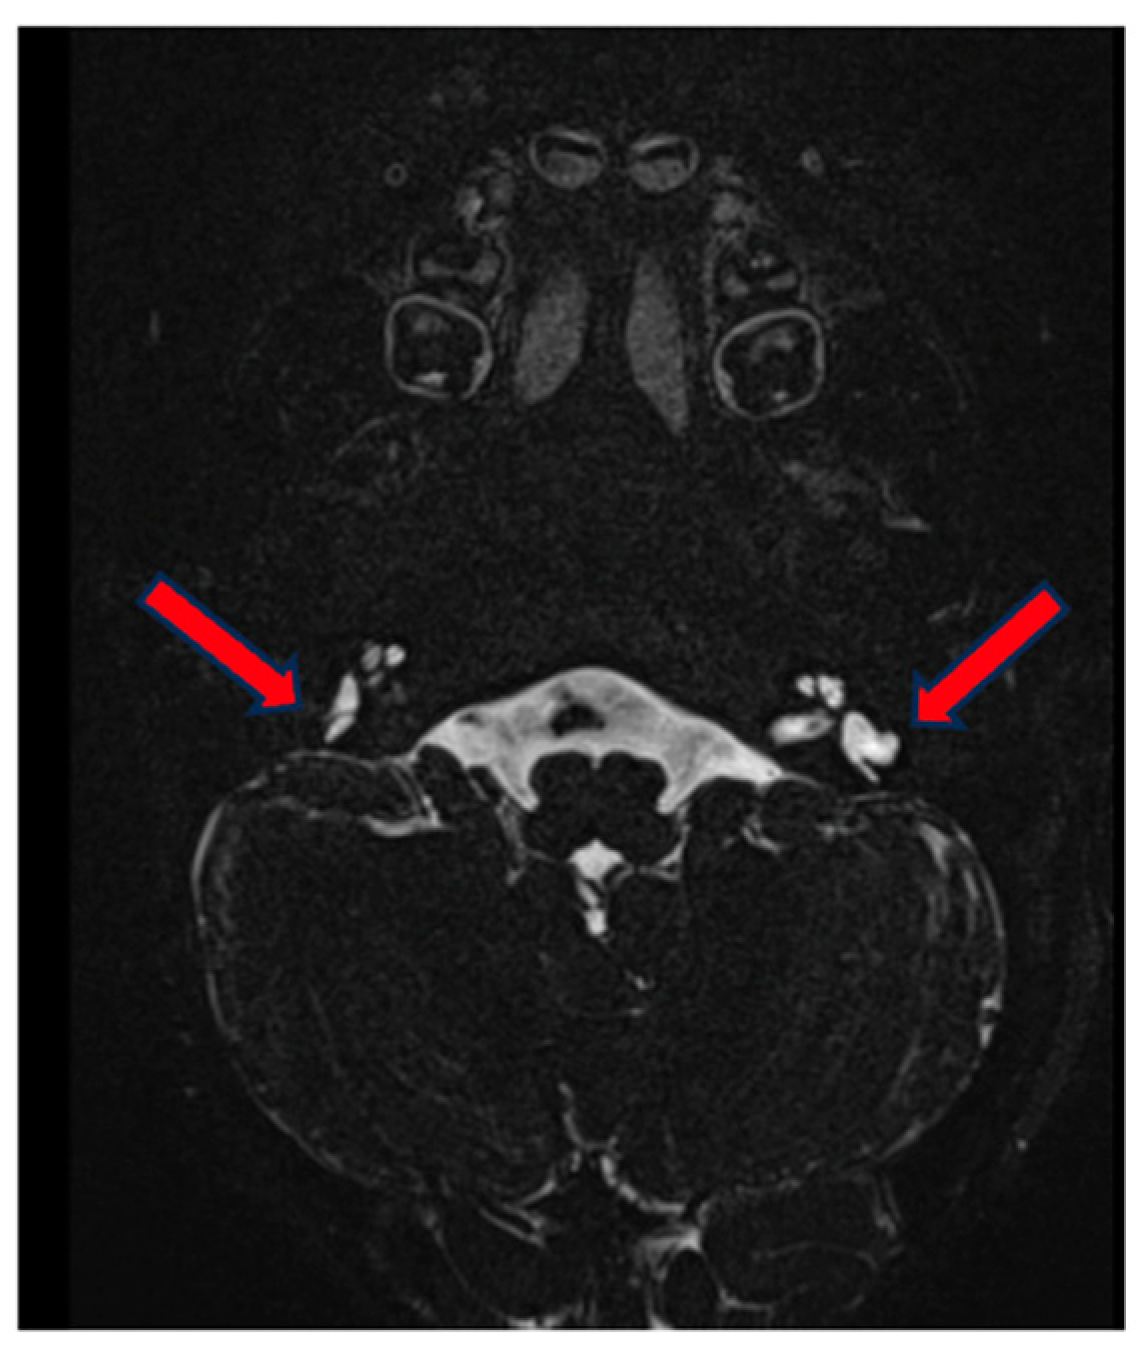

MRI correlated to the findings of the vestibular exam, revealing a normal fluid signal in the cochlea and vestibulum, as well as in the upper semicircular canal. Aberrant morphology with a blunt appearance of the lateral semicircular canal, which lacks a central opening, and partly also of the posterior semicircular canal, which appears smaller, with abnormal morphology and loss of the circular aspect. No widening of the vestibular aqueduct (Figure 4). There is a suspicion of hypoplasia of the left cochlear nerve, whereas the cochlea appears normally developed (Figure 5).

Figure 4.

MRI of the inner ear for case 2, T2 tse3d weighted image, dysplasia of lateral semicircular canals (red arrows).